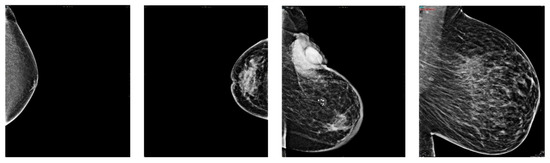

3.1. Dataset Descriptions

3.3. Preprocessing